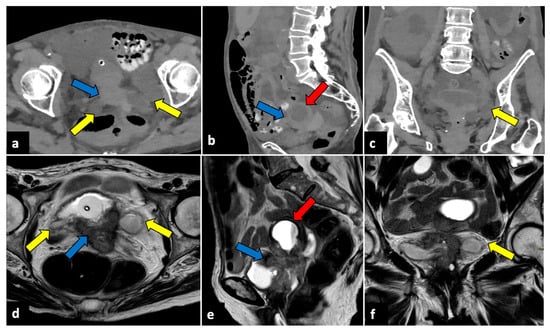

US combined with colour Doppler is the first-line imaging of choice, and the findings depend on the duration and severity of the torsion. Typical findings are an enlarged (>4 cm), oedematous, and heterogeneous ovary found in an unusual location, for instance, shifted medially or cranially to the uterine fundus. The ovary usually shows a hyperechoic central stroma with peripherally displaced follicles (follicular ring sign) [24]. An underlying ovarian lesion may be seen. Upon the Doppler evaluation, a reduced or absent vascular flow is typically observed, and the twisted vascular pedicle could be seen as whirlpool sign. Free fluid is often observed (Figure 1) [25,26].

Figure 1.

Ovarian torsion in an eight-year-old patient presenting at the emergency department with aching right pelvic pain for a few hours. Transabdominal US examination (a,b) shows that the right ovary is grossly enlarged (long axis: 42.9 mm; short axis 34 mm) and abnormally located in the midline. The ovary appears slightly echogenic, with many small cysts at the periphery (yellow arrow). Small volume free fluid with tiny echoes is present in the pelvis (red arrow). During the Doppler US evaluation, no vascular flow was noticed (not shown).